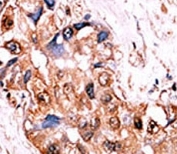

IHC analysis of FFPE human hepatocarcinoma tissue stained with the phospho-Src antibody.

IHC (Paraffin) : 1:50-1:100